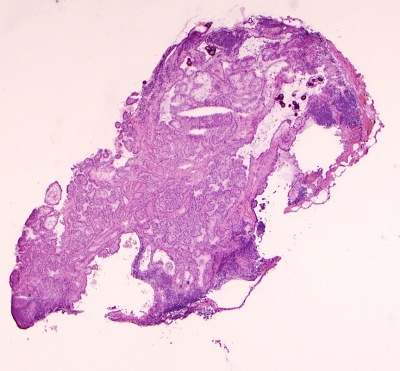

Papillary Carcinoma of Thyroid-Frozen Section. (Low Power.)

Low power view of papillary carcinoma in frozen section. Note the psammoma bodies and papillary architecture.

Keywords: Papillary Carcinoma, Frozen Section, Low Power